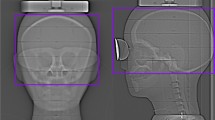

An anthropomorphic Rando phantom (Phantom Laboratory, Salem, NY, USA) representing the skull and trunk of a 175-cm tall male weighting 73.5 kg was manufactured on demand in one piece to study the effect of selective shielding on image quality and absorbed dose. The phantom is composed of synthetic materials representing the density and X-ray attenuation of lung tissue and soft tissue and includes a human skeleton [11]. Two breasts modules composed of tissue-equivalent material (bees wax) of 260 cm3 each could be added to the phantom.

Multislice CT scans, acquisition and reconstruction

For the purpose of dose calculations and assessment of image quality, multislice CT (MSCT) scans of the phantom were obtained at an Aquilion16CFX scanner (Toshiba, Japan) (120 kVp, 16×1 mm, 100 mAs). The scan field of view (SFOV) was 400 mm. A total of 259 images were reconstructed as 4-mm thick contiguous slices covering the entire phantom. The reconstructed field of view was 400 mm, and a 5122 image matrix was used. Scans were made of five different configurations; each scan was repeated twice in order to enhance the accuracy of noise assessment. The selected scan configurations included two acquisitions without shielding, i.e., respectively with and without the breast modules, and three configurations with shielding, i.e., respectively with the eye-lens shield, the thyroid shield, and the breast shield.

For dosimetry purposes, voxel phantoms were derived from the CT scans of the anthropomorphic phantom. Original axial images were reduced to 256×256 pixels; corresponding voxels measured 1.6×1.6×4 mm3. The location of the eye lens and thyroid within the voxel phantom were established by a radiologist (AS). Breast tissue and lung tissue could be easily distinguished.